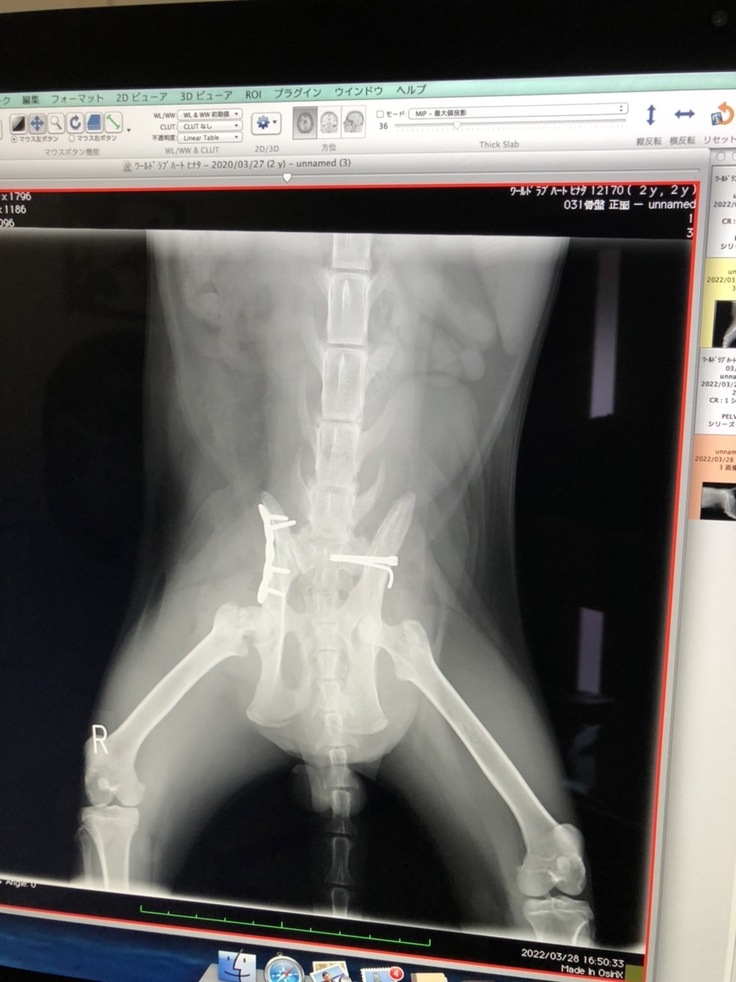

手術内容 ⑴骨盤骨折:右腸骨体骨折はプレート固定、左仙腸関節脱臼は元の場所に戻してスクリューで固定してもらいました。 ⑵右大腿骨頸部骨折:事故から2週間以上経っていて治ってきているのでこのまま自然治癒という形をとります。将来関節炎になる可能性があるとのこと。大変な手術でしたが、日向は頑張りました。病院でも看護師さんになつき、順調な回復を見せました。

手術後のレントゲン写真と日向